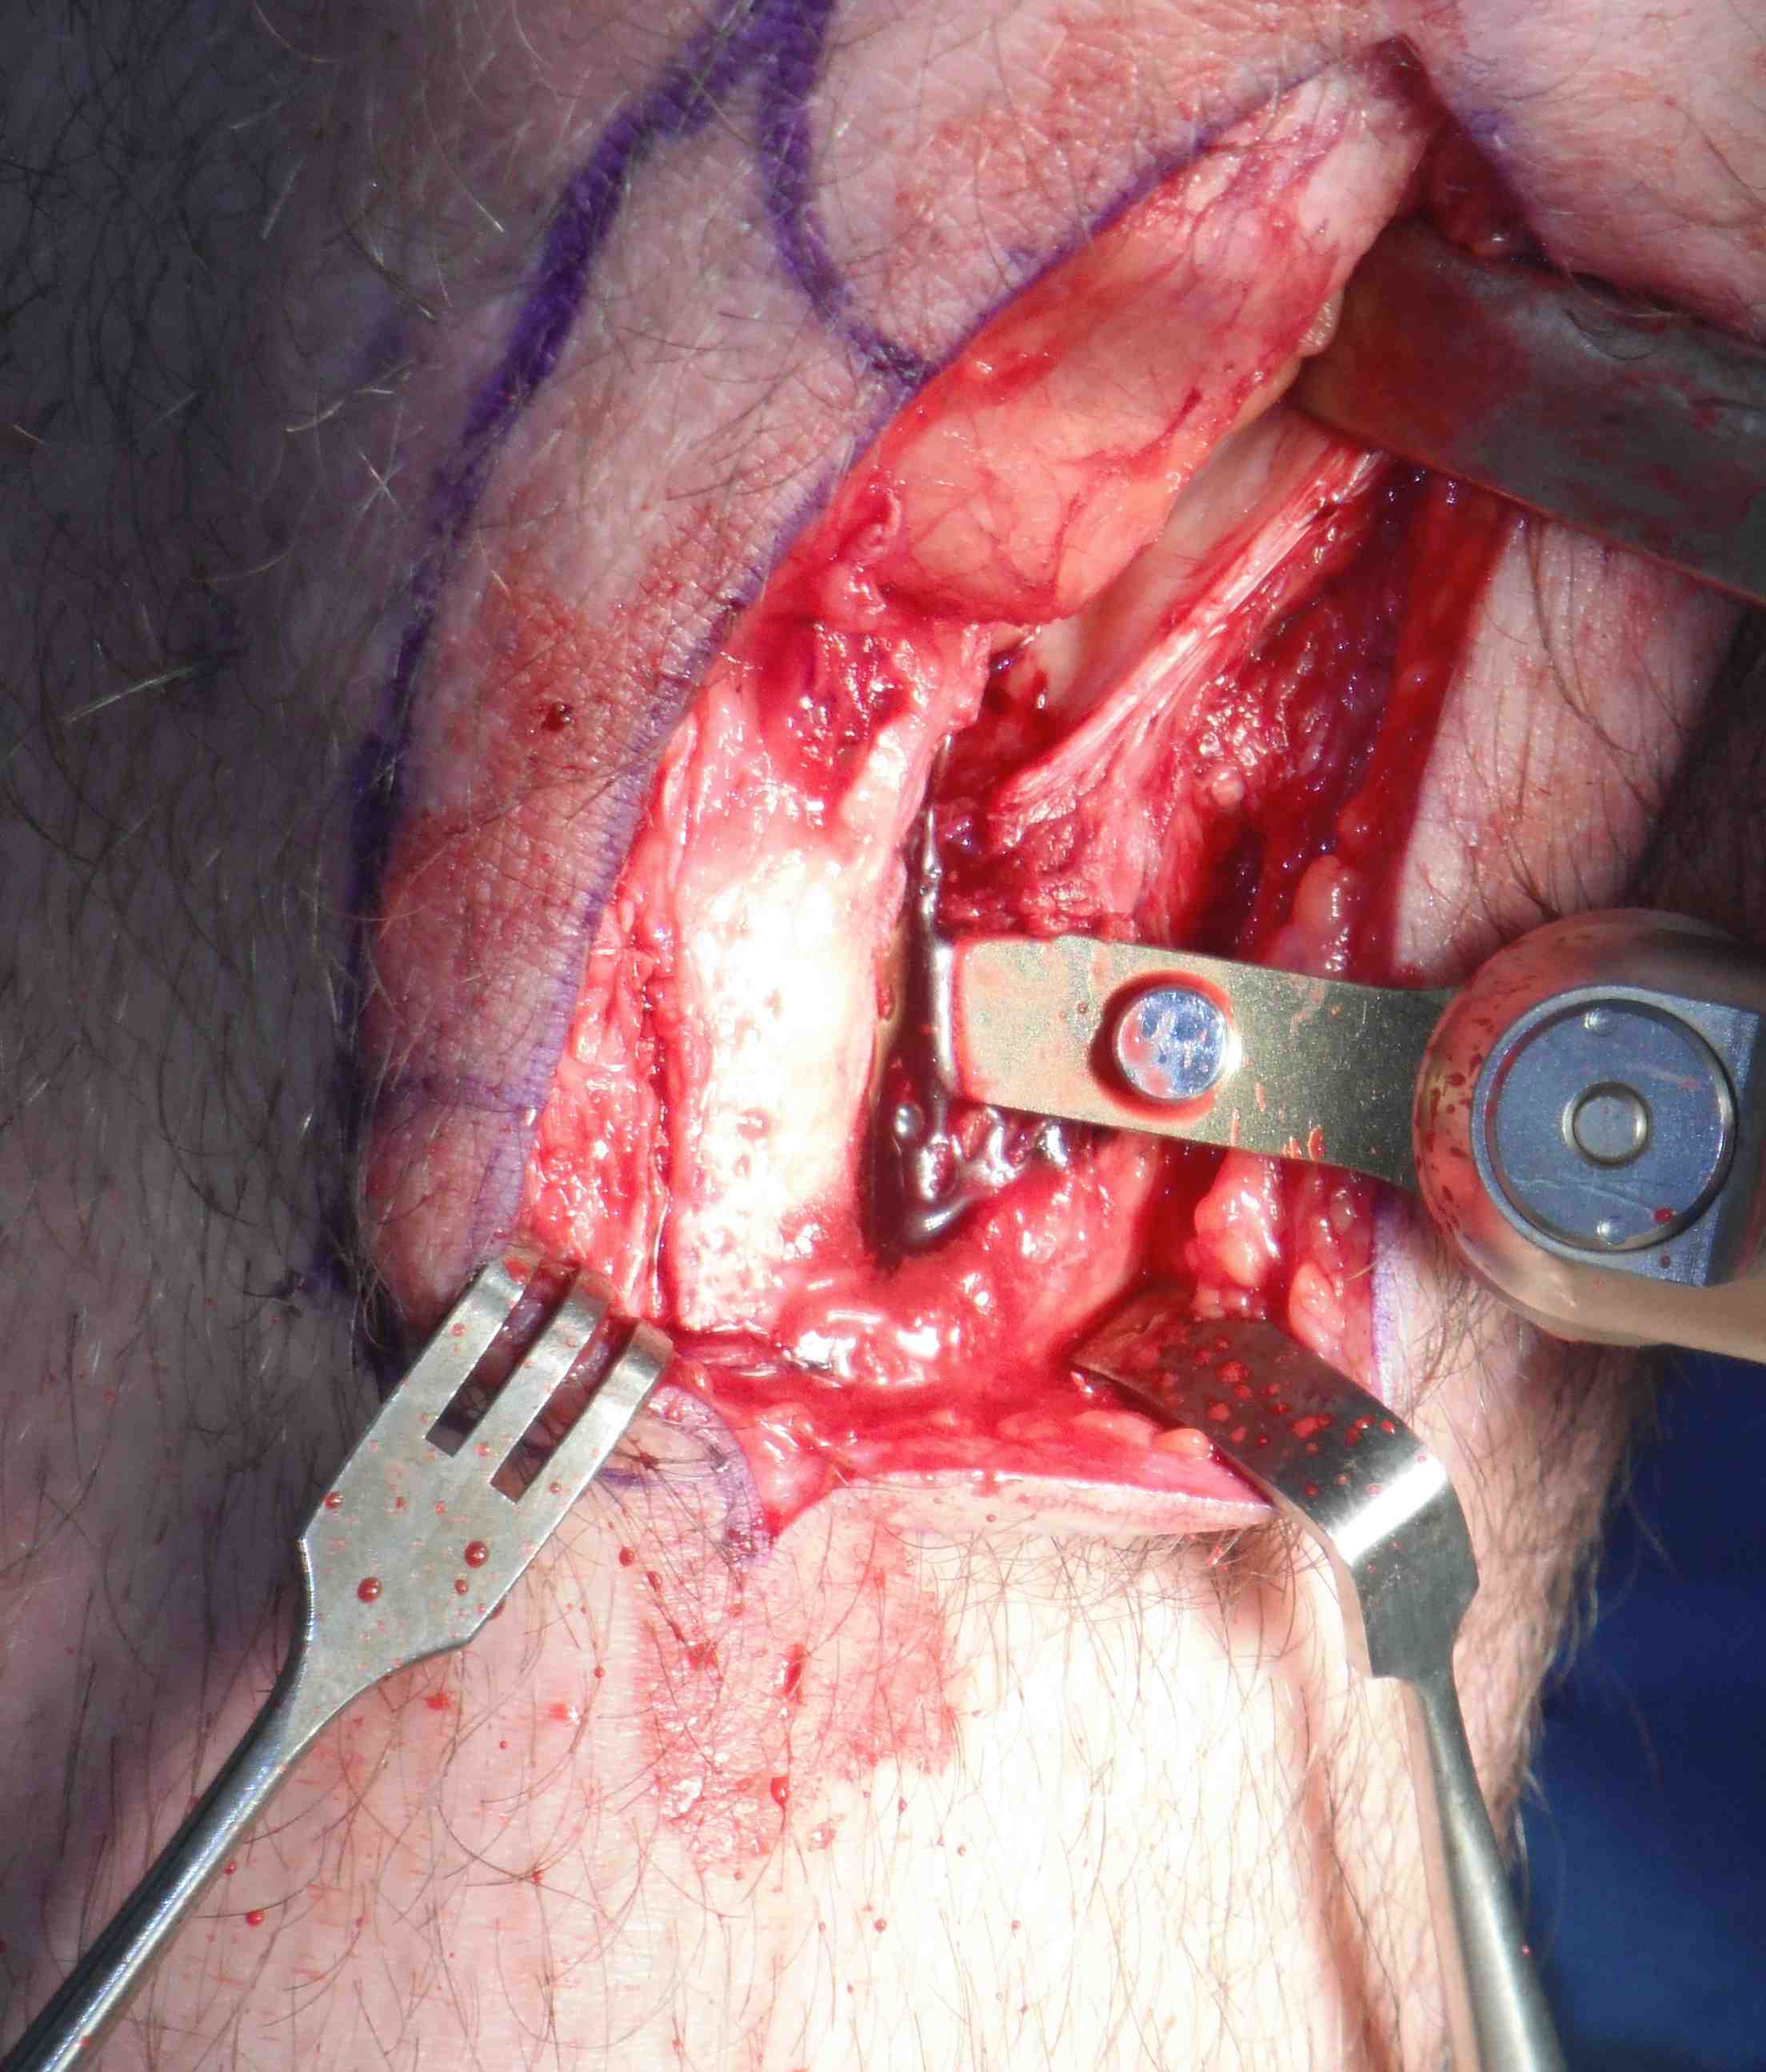

Bone blocks

- measure 2 x 1 cm bone block on tibial tuberosity

- cut each side at 45o with saw

- 1cm deep with each saw cut meeting as triangle

- distal transverse cut 1cm deep

- lever out with curved ostetome

- make 2 x 1.5 cm drill holes with piece in situ, mark with pen

Repeat on patella side, can push patella down for exposure

- use smaller lever on patella side and be more delicate

- remove graft carefully, have to dissect off the fat pad